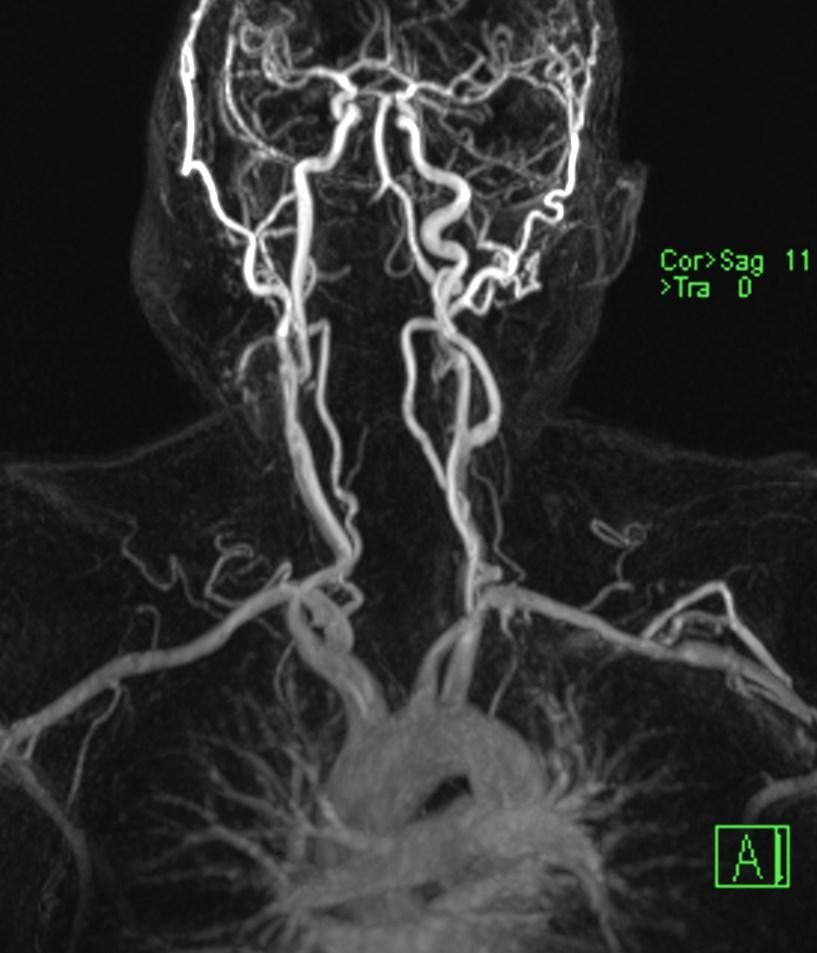

MR angiography showing the absence of flow in right VA (arrows).